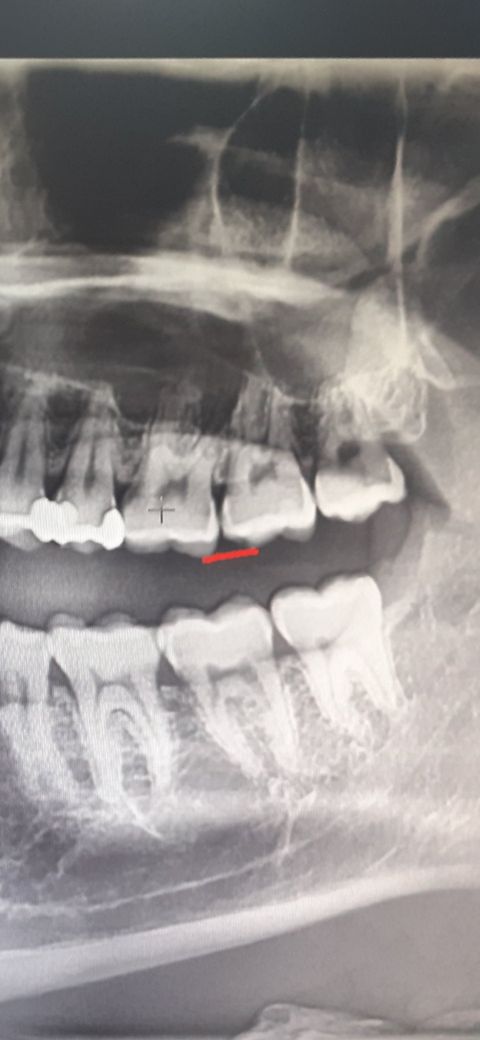

이 충치 심하지 않은데 불편 합니다.

빨간표시 이 충치 심하지 않아서 의사선생님이 지켜 보자고 합니다. 하지만 이 충치쪽 자꾸 은근 애매하게 통증이 있는데 치료해야 하나요? 아니면 이 충치가 아니라 다른게 있어서 통증 있는건가요? 크랙(치아균열) 이라든지

해당 치아의 잇몸 안쪽 치아면에 마모 또는 치아가 깨져 나간 부위가 있는 것처럼 보이나 실제 치아를 확인하지 않고 판단할 수 없습니다.

질문하신 것처럼 크랙이 있다 하더라도 수직적인 크랙인 경우에는 방사선 사진상 알 수 없으며, 수평으로 크랙이 있는 경우에도 크랙이 상당히 진행되어야 알 수 있습니다.

현재 말씀하시는 치아의 옆쪽이 충치가 눈에 보입니다.

신경과 매우 근접해 보이며 통증이 느껴질 정도로 보여집니다. 치과의사선생님마다 치료 계획이 다를 수 있어 보이나 현재 상황으로 보아서는 신경치료를 동반한 충치 치료를 해야할 것으로 보이며 크라운도 하셔야할 것으로 판단됩니다.

통증이 너무 불편하다면 적극적인 치료가 필요해보이는 치아입니다.

파노라마 엑스레이 상에서 미약한 인접면 우식증으로 의심되는 부분이 보이기는 하지만 해상도가 낮기때문에 정확하게 진단하기는 어렵습니다. 바이트윙 엑스레이나 스탠다드 촬영을 통해 정확히 진단하는게 좋아보입니다. 또한 크랙은 엑스레이에서 일반적으로 나오지 않습니다.